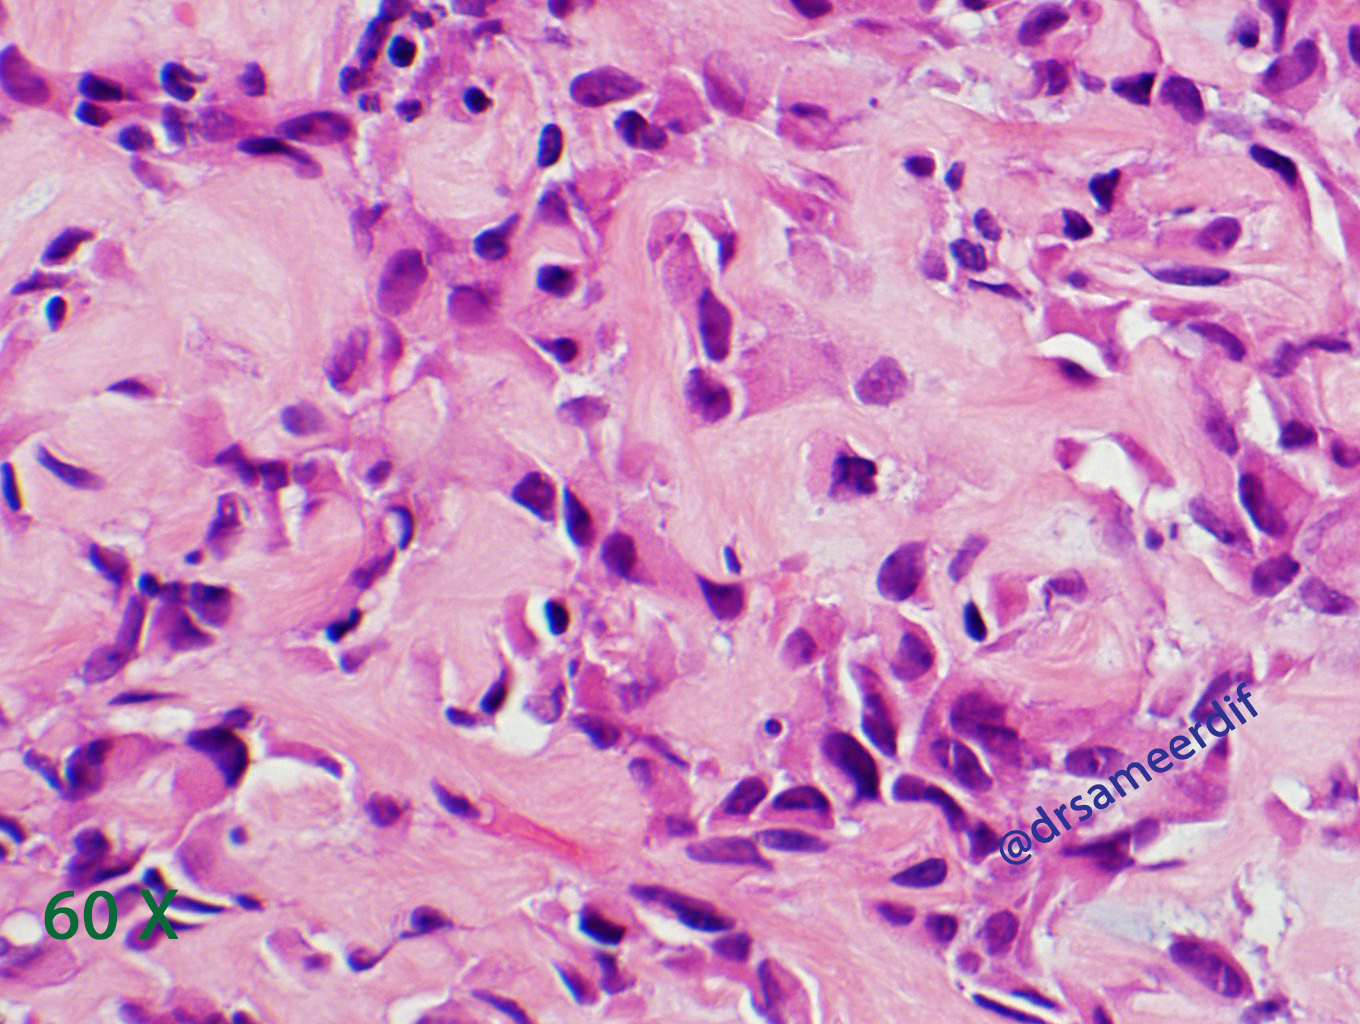

The current biopsy shows a densely hyalinized sclerotic matrix, with focal areas reminiscent of osteoid, lined by small to medium-sized epithelioid cells with clear to eosinophilic cytoplasm and bland nuclei. Mitotic figures are inconspicuous. By immunohistochemistry, the neoplastic cells are positive for MUC4, but negative for CK7, CK20, SATB2, and calcitonin. The morphology and immunohistochemical results are diagnostic of metastatic sclerosing epithelioid fibrosarcoma (SFE) from primary know SFE of the soft tissue.

- Nests and cords of small to medium size, round- oval nuclei with scant clear to pale cytoplasm

- Hyalinized stroma, which may resemble osteoid. Sometimes cartilaginous and osseous metaplasia may be seen and it may show focal myxoid change or calcification.